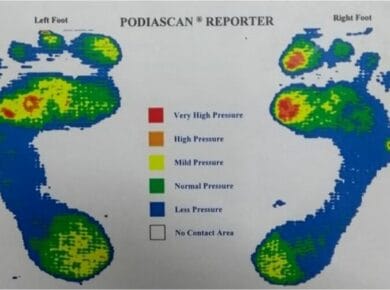

Η κύρια αιτία που την προκαλεί είναι η συνεχής πίεση και καταπόνηση της φτέρνας. Όταν περπατάμε, τρέχουμε ή στεκόμαστε όρθιοι για πολλές ώρες, οι τένοντες και οι ιστοί κάτω από το πόδι μας καταπονούνται. Αυτό μπορεί να οδηγήσει σε μικροτραυματισμούς, οι οποίοι με τον καιρό προκαλούν τη δημιουργία αυτής της οστικής προεξοχής. Επιπλέον, άνθρωποι με πλατυποδία, αυξημένο σωματικό βάρος ή ακατάλληλα παπούτσια διατρέχουν μεγαλύτερο κίνδυνο να την εμφανίσουν.

Η αντιμετώπισή της ξεκινά με συντηρητικά μέτρα. Τα πιο βασικά είναι η χρήση ειδικών πάτων που μειώνουν την πίεση στη φτέρνα, η εφαρμογή πάγου για τη μείωση του πρηξίματος και οι διατάσεις για την ενίσχυση των μυών του πέλματος και της γάμπας. Αν ο πόνος είναι έντονος, μπορούν να χρησιμοποιηθούν αντιφλεγμονώδη φάρμακα ή φυσικοθεραπείες, όπως τα κρουστικά κύματα. Μόνο σε πολύ σοβαρές περιπτώσεις μπορεί να χρειαστεί χειρουργική επέμβαση.